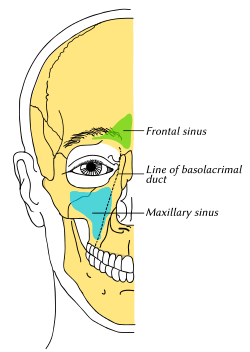

Outline of bones of face, showing position of air sinuses. Maxillary sinus is shown in blue. | |